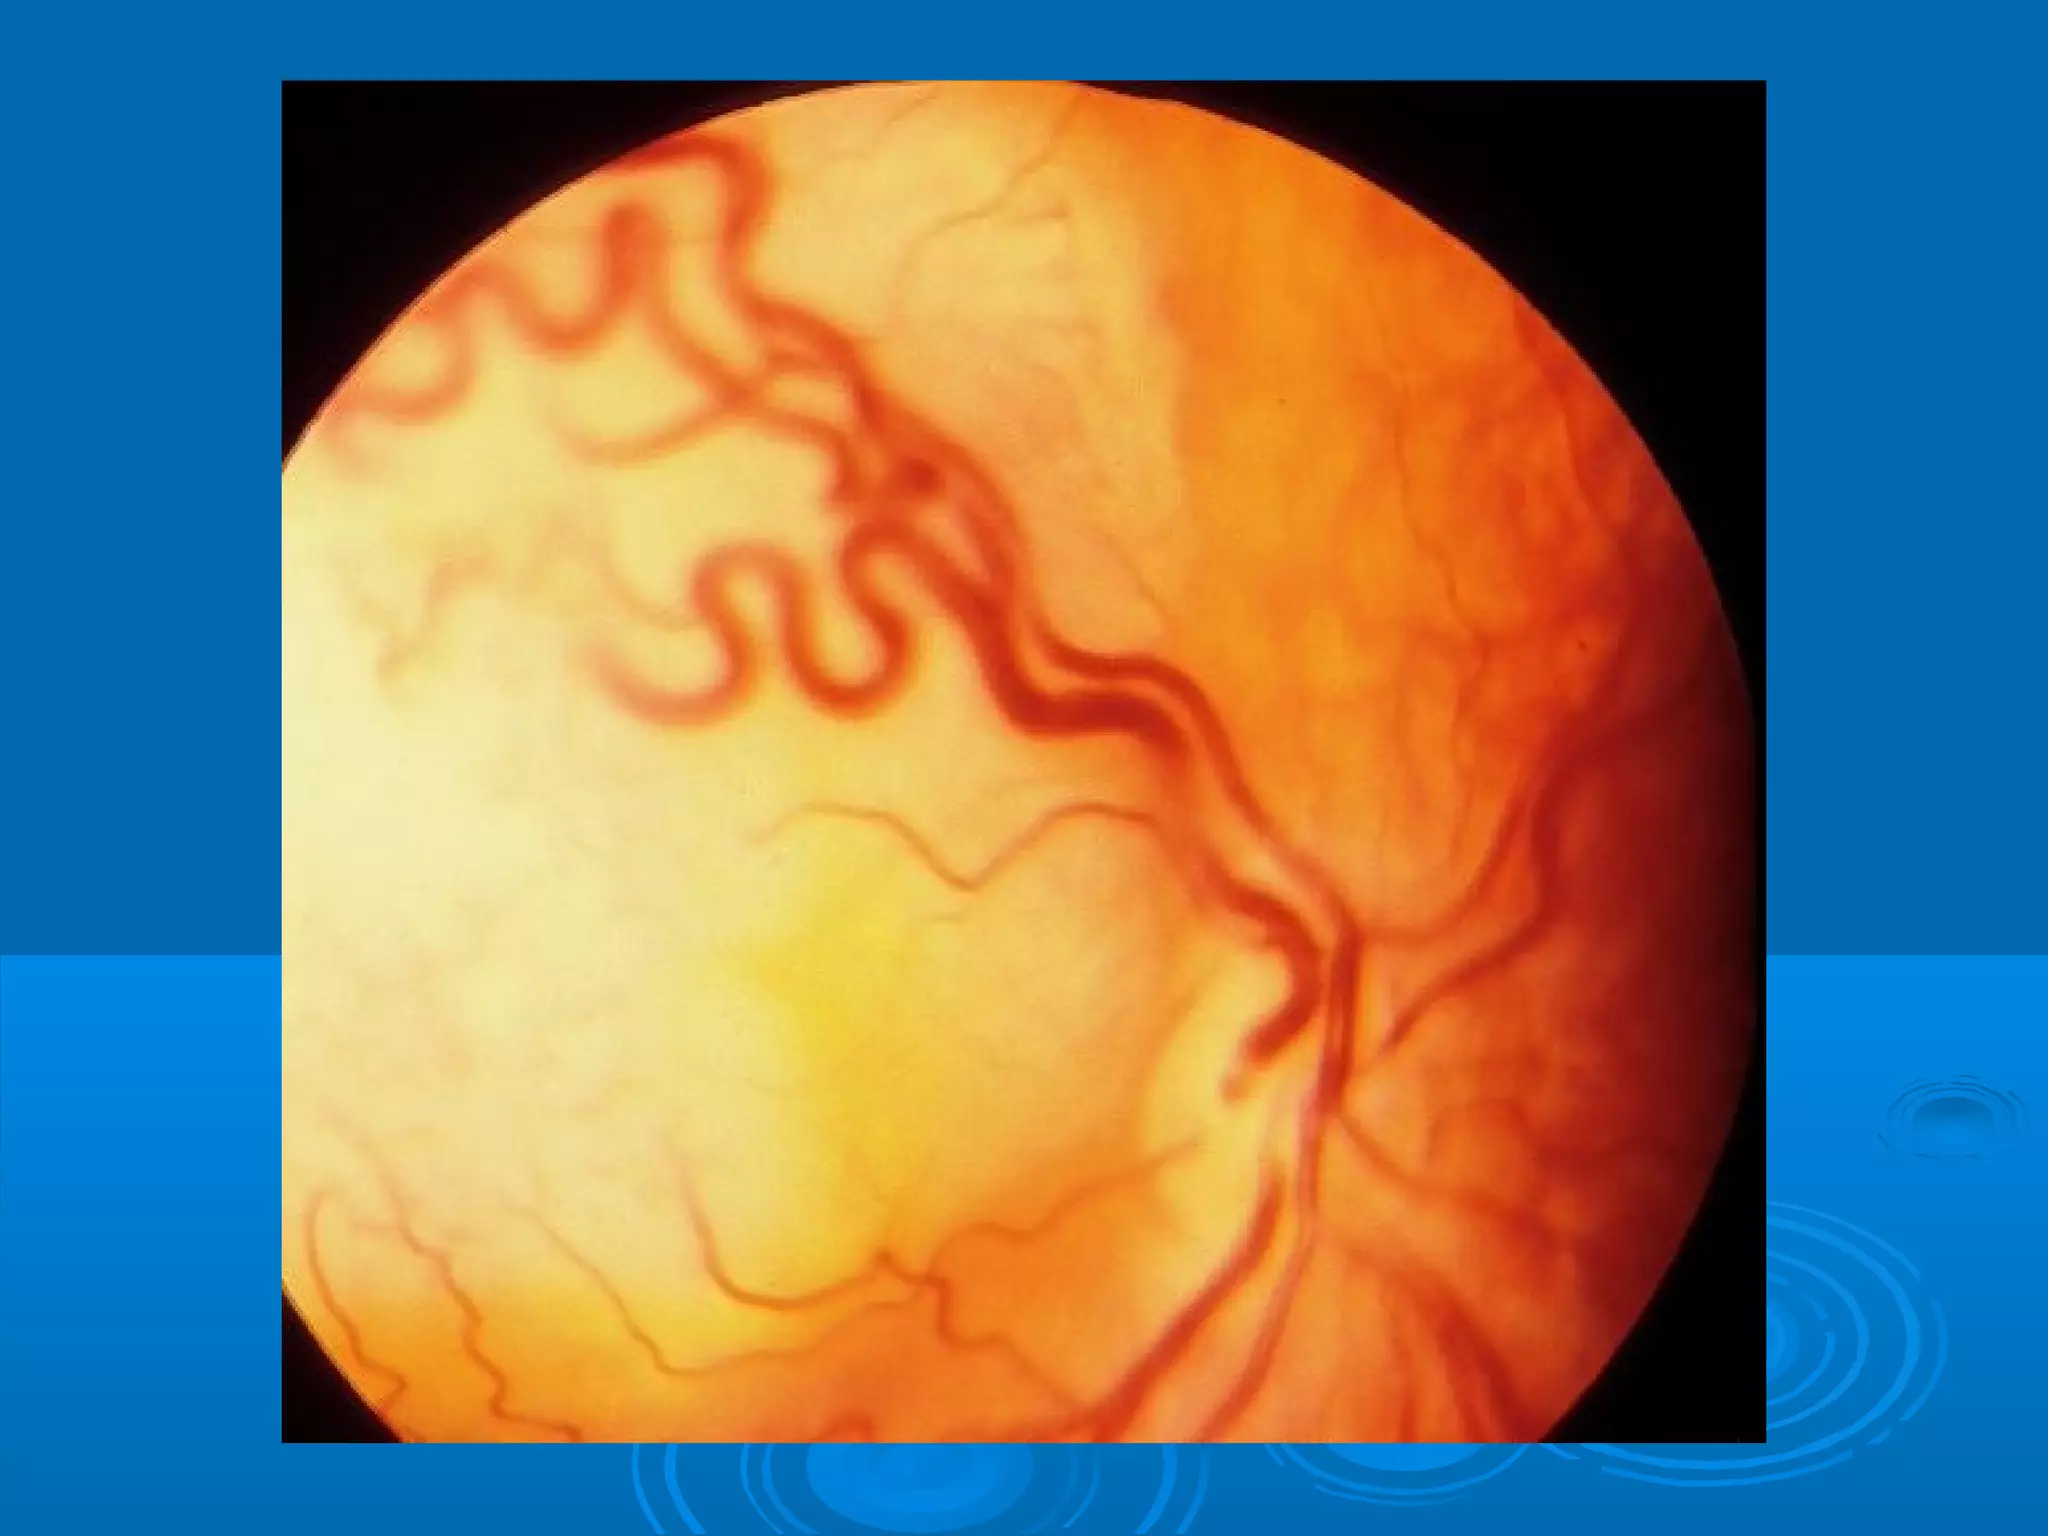

Болезнь Коатса - это идеопатическое заболевание, характеризующееся полиморфными изменениями сосудов сетчатки с массивной экссудацией, чаще всего у детей и подростков, с преобладанием среди мальчиков. Эпидемиология показывает, что заболевание проявляется, как правило, в возрасте 8-16 лет, но возможно его обнаружение и у взрослых. Основные проявления включают ретинальные аномалии, субретинальную экссудацию и постепенно прогрессирующую потерю зрения.